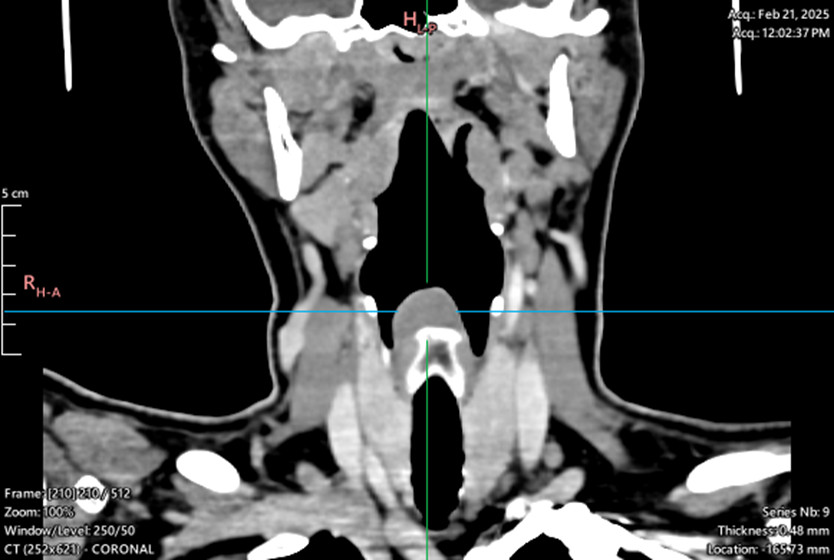

Laryngeal tumor - posterior commissure

Biopsy, granular cell tumor, granular cell myoblastoma, Abrikossoff tumor/div>

Symptoms: hoarseness, sensation of a foreign body in the throat, dysphagia